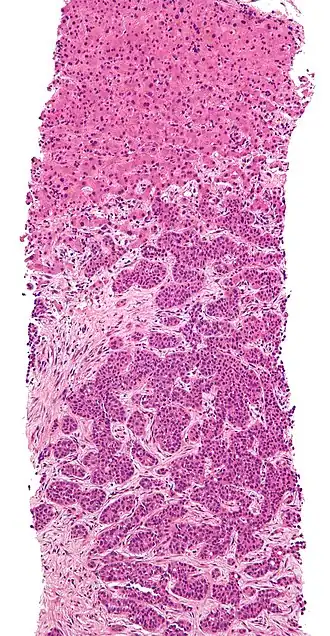

The cells in a metastatic tumor resemble those in the primary tumor. Once the cancerous tissue is examined under a microscope to determine the cell type, a doctor can usually tell whether that type of cell is normally found in the part of the body from which the tissue sample was taken.

For instance, breast cancer cells look the same whether they are found in the breast or have spread to another part of the body. So, if a tissue sample taken from a tumor in the lung contains cells that look like breast cells, the doctor determines that the lung tumor is a secondary tumor. Still, the determination of the primary tumor can often be very difficult, and the pathologist may have to use several adjuvant techniques, such as immunohistochemistry, FISH (fluorescent in situ hybridization), and others. Despite the use of techniques, in some cases the primary tumor remains unidentified.